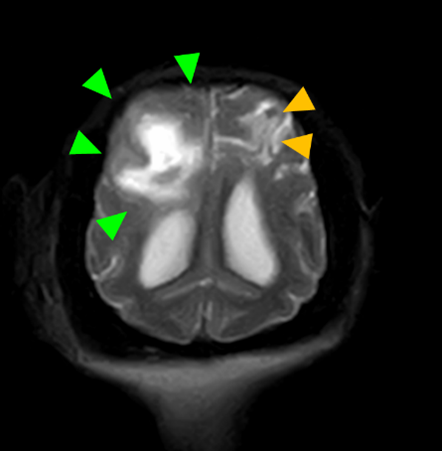

犬種 チワワ

年齢 7歳齢

体重 2.95kg

性別 去勢雄

運動失調(ふらつき、登れていた段差も登らなくなった)の主訴で来院。

初診から4か月後に重積発作で来院されたため、MRI検査を実施。

MRI検査:

右前頭葉にT2 強調画像/FLAIR 画像で高信号、T1 強調画像で一部低信号を示し、辺縁部で一部造影増強を示すびまん性の所見を認めた。この所見は、DWI 画像で高信号、ADC-map で大半が等~低信号を示していた。また左側前頭葉にも同様の信号所見を示す微小病変を認めた。

造影T1強調画像 水平断像